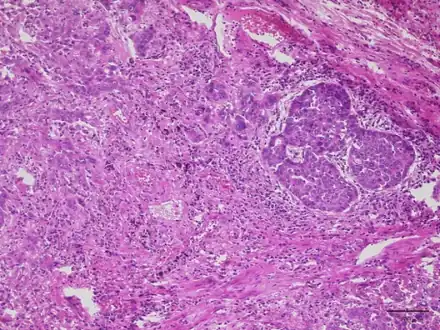

Lung adenocarcinoma with Lambert Eaton myasthenic syndrome-lesion shows proliferation of infiltrating atypical epithelial cells with cribriform or papillary structures